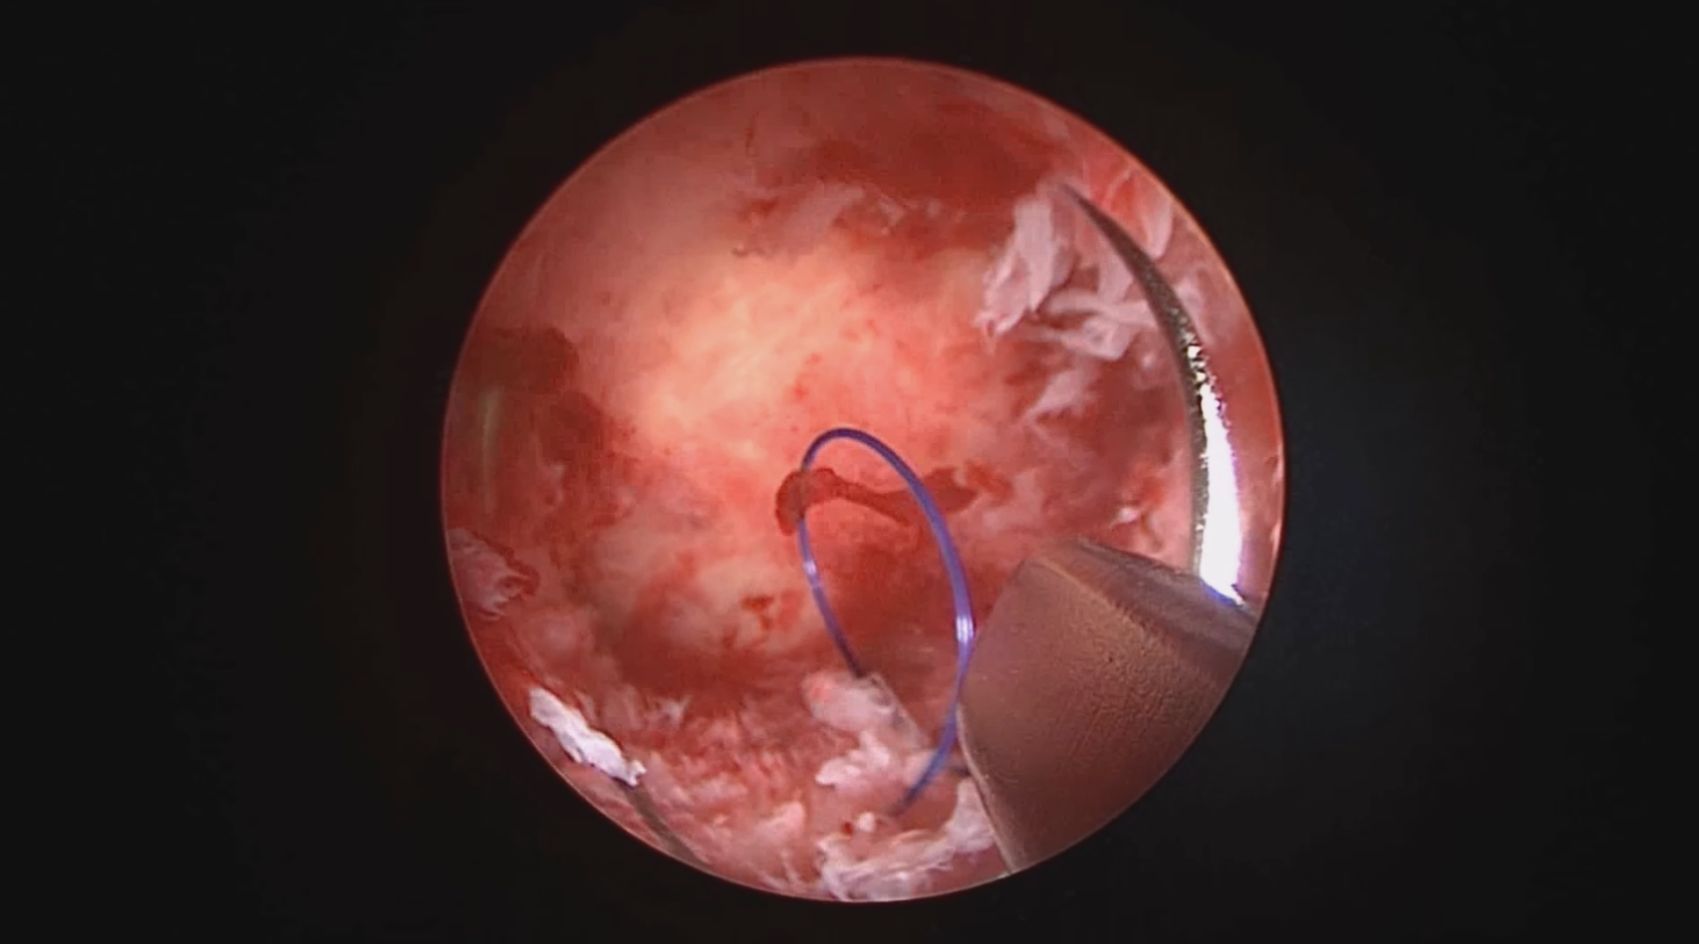

患者38岁,G2P1,剖宫产1次。安环13年,发现内膜息肉3年伴月经淋漓不净。2025年3月行宫腔镜取环、息肉切除,同时放置曼月乐环并固定。子宫后位,宫深7.5cm,宫型环位置正常,宫颈管及宫腔后壁见息肉,顺利取出节育环,切除息肉送病检,4-0不可吸收线将曼月乐缝合固定于宫腔上段后壁,第一次做宫腔镜下缝合固定节育环,体外打结后推结到位比较困难,今后改进缝合固定方式。病检为子宫内膜息肉及增殖期子宫内膜。2025年4月复查B超,曼月乐位置正常,环顶端距宫底1.3cm。